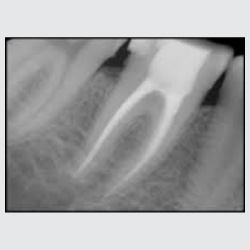

Root Canal Treatment

• Root Canal Treatment, commonly called RCT is removal of infected soft tissue within the tooth and its replacement with an artificial inert material.

• RCT is done when the tooth decay, if left untreated, reaches the pulp of the tooth. The pulp is the soft tissue present in canals of the tooth and consists of nerves and blood vessels.

• This infection gives rise to dental pain. The infected part of the pulp is therefore removed and the canals are cleaned before being filled with a filling material.

• It is a 30 minute procedure performed under local anaesthesia.

• Contrary to the popular belief, with the advent of newer techniques and medications, RCT is painless and comfortable.